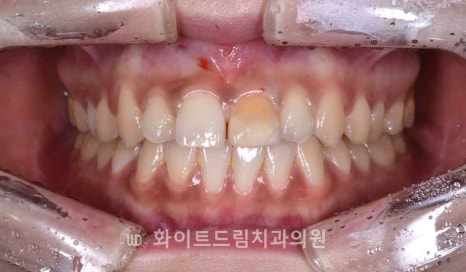

▲ 강남역앞니치과, 치료 전 초진 (23.09.12)

위 환자분도 이런 원인으로 인해

눈에 잘 보이는 앞니가 옆 자연치 색상과 어울리지 않고

도드라져 웃을 때마다 유독 한 치아만 눈에 띄어

심미적인 불편감을 크게 느끼게 되신 것이었죠.